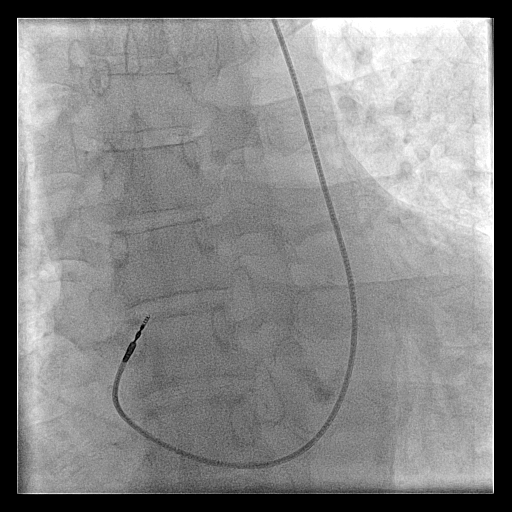

Extra loop

alpha_loop.jpg